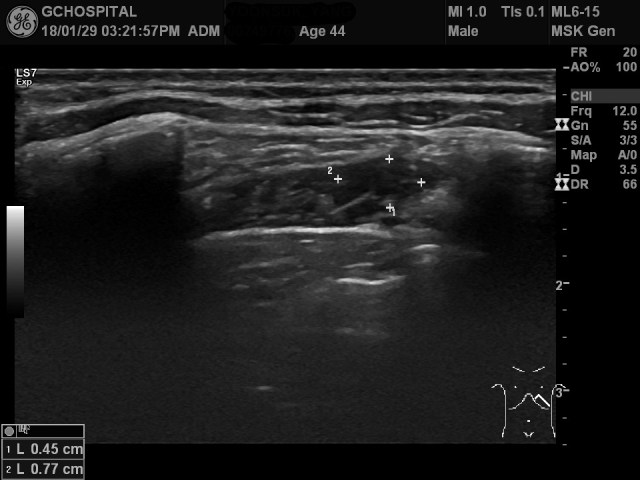

모니터나 컴퓨터가 적절하게 세팅되있지 않으면 미세한 차이를 구분하기가 쉽지 않습니다. 쉽게 확인하지 못하신 분들은 앞서의 영상에서 주변보다 에코가 낮고 내부의 architecture가 잘 구분되지 않은 부위를 표시했으니, 이걸 보면서 비교해 보시면 차이가 있다는 것을 느끼실 수 있을 것입니다.

이 환자는 늑골 어디에도 골절소견이 없었으며, 이렇게 늑간근 내층(internal layer)에 국소적인 에코변화가 있는 부위와 일치하는 곳에 국소적인 압통(tenderness)을 호소하였기 때문에 교통사고 당시 받았던 손상이 앞쪽 흉벽 중에서도 늑간근에 국소적인 출혈 내지 근육손상을 일으킨 것으로 결론을 내리고, 검사 전에 했던 rib series와 chest PA view 외에 더이상의 영상검사는 추가로 시행하지 않았습니다.